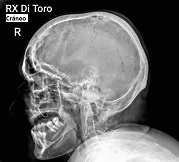

Utilizamos sensores Flat Panel, que nos permiten acortar al Máximo el tiempo de exposición (Dosis de Radiación) y obtener la adquisición inmediata de las imágenes.